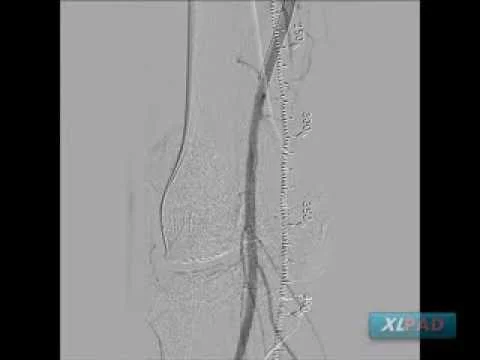

Mid SFA CTO Treated with Negotiating Side Branch

Proximal to Distal SFA CTO Treated with Viance